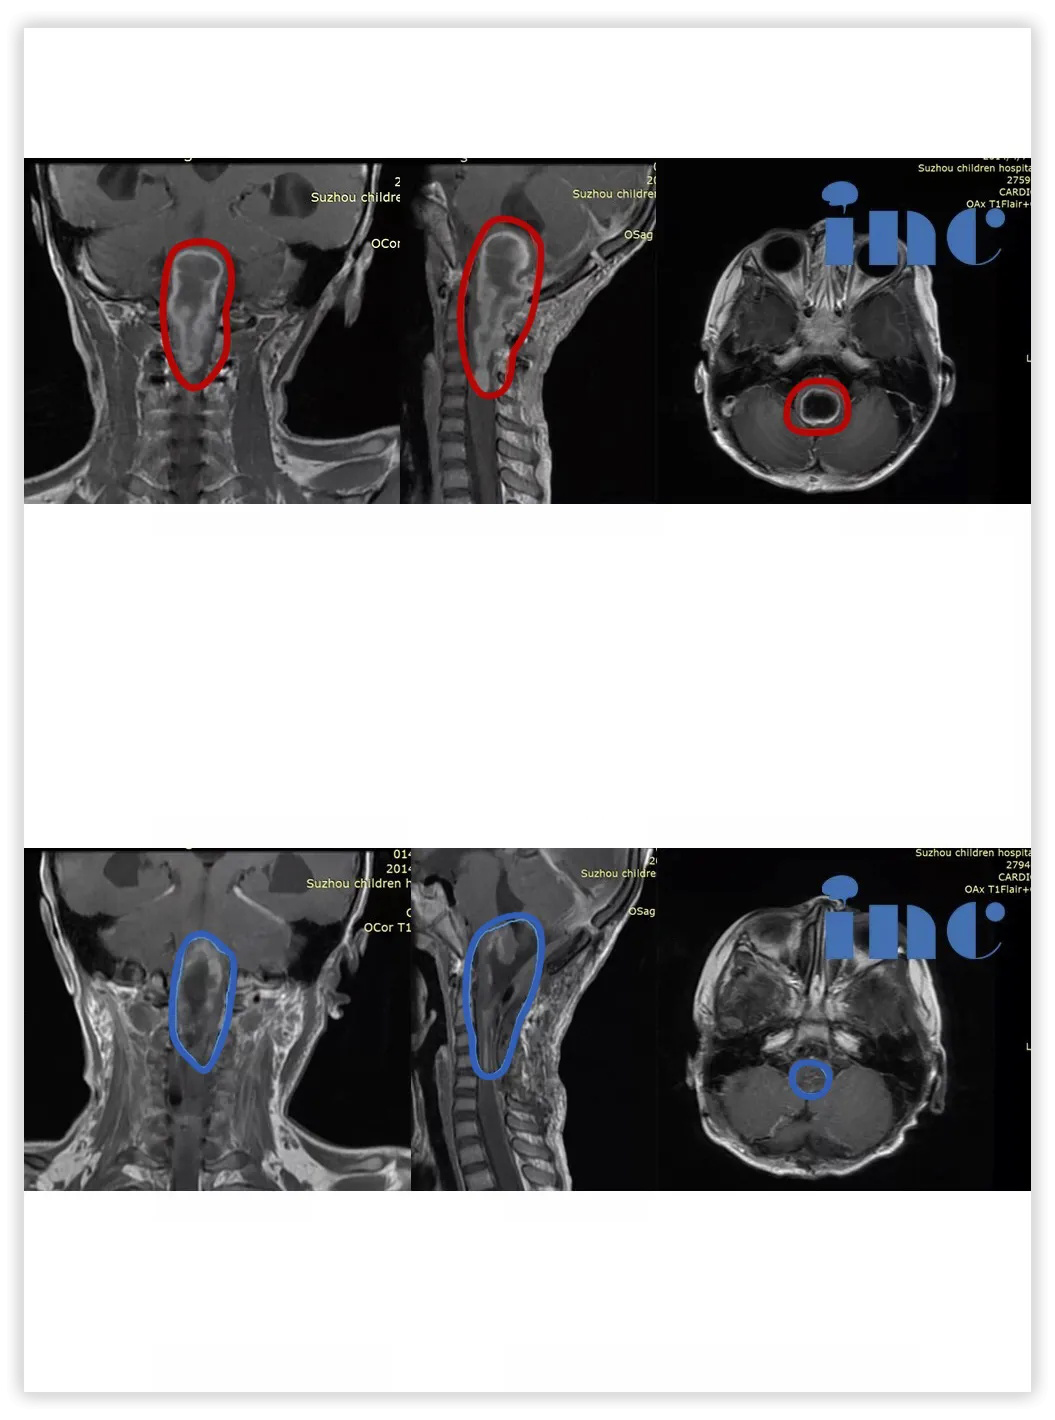

3、5岁女孩——脊髓-脑干毛细胞星形细胞瘤

病情回顾:右侧肢体无力伴有吞咽困难2月,伴有呕吐、头痛。为了减轻脑积水,于某医院行右侧脑室腹腔内分流术,行MR提示脑干胶质瘤、脊髓胶质瘤。症状加重趋势明显。如不手术,孩子将有生命危险。

治疗难点:脑瘤较大、病变范围广,位于脑干延髓一直延伸至颈5节段脊髓,这是人的呼吸、循环、颅神经、肢体功能等众多神经核团及传导束所在部位,想要较大水平全切肿瘤并保护众多神经核团及传导束难度较大,可能面临脑干水肿、呼吸功能障碍、后组脑神经功能障碍、脑积水,严重者有意识障碍、肢体瘫痪等并发症,也正因此,国内医生均表示风险太大,无手术机会……

手术结果:巴教授主刀,肿瘤次全切(95%以上)。术后ICU留观1天,神志清楚,完全自主呼吸,拔除插管,生命体征平稳,转入普通病房。患儿右侧肢体活动度、肌力较术前明显好转。术后1周,患者下地自行行走,无手术并发症出现。术后3周出院,术后2月可如同龄患儿生活。术后3年,琦琦可以像正常孩子一样玩耍。